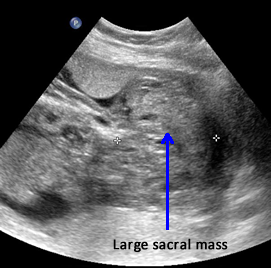

Above. Case 3. 25 4/7 weeks gestation. Sacrococcygeal teratoma. Large mass measuring 5.9 x 10.9 x 8.3 cm, which is noted in the sacral area, but also extends internally superior to the bladder.

Above. Case 3. 25 4/7 weeks gestation. Sacrococcygeal teratoma. Color Doppler indicates the vascular nature of the external portion of this tumor.

Above. Case 3. 25 4/7 weeks gestation. Sacrococcygeal teratoma. Coronal scan demonstrates internal extension of the tumor to the lower abdomen superior to the bladder and within the bounds of the 2 umbilical arteries. This tumor represents a Type 2 sacrococcygeal teratoma (extension to the abdomen).

Above. Case 3. 25 4/7 weeks gestation. Sacrococcygeal teratoma. Transverse of the abdomen demonstrates fetal ascites and likely fetal hydrops.